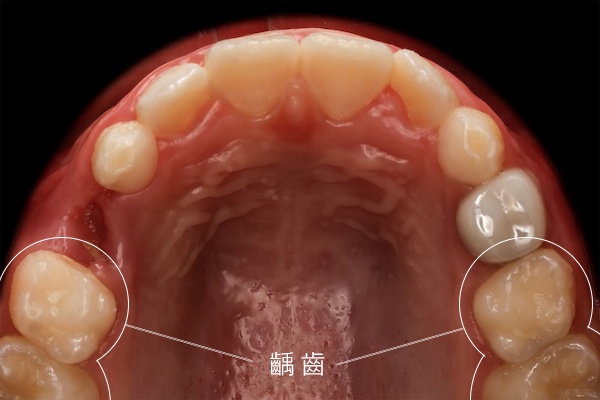

上鏡無死角:全瓷美學牙冠

「考量努拉平時有上鏡需求,這次在修復方式的選擇上,我們特別重視整體美觀的呈現。」陳醫師特別提到,由於努拉的蛀牙位置較偏前側,為了維持自然的視覺感,這次捨棄了傳統的銀色小鋼牙,改選全瓷美學牙冠修復。這不僅提供了極高的硬度保護,色澤也與原生牙完美融合,讓努拉醒來後依然能大方展現笑容。

Camera-Ready: Aesthetic All-Ceramic Crowns "Considering Nuala’s need to be on camera, we placed special emphasis on the overall aesthetic presentation when choosing the restoration method." Dr. Chen specifically mentioned that because Nuala's cavities were closer to the front, they ditched traditional silver "stainless steel crowns" in favor of aesthetic all-ceramic crowns to maintain a natural look. These provide high-strength protection and blend perfectly with her natural tooth color, allowing Nuala to smile confidently as soon as she woke up.